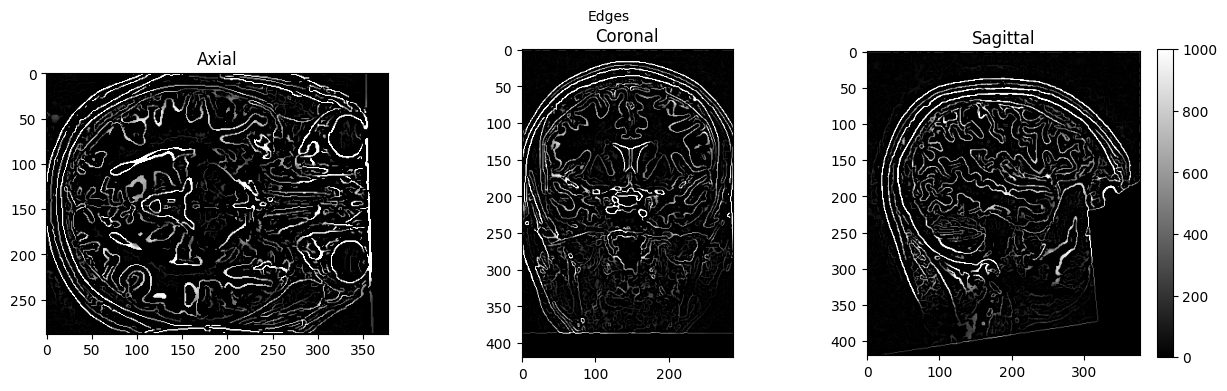

edge3 = afni.Edge3()

edge3.inputs.in_file = './sub-01_ses-01_7T_T1w_defaced.nii'

edge3.inputs.out_file = './sub-01_ses-01_7T_T1w_defaced_edges.nii'

edge3.inputs.datum = 'byte'

res = edge3.run()

edges = nib.load('./sub-01_ses-01_7T_T1w_defaced_edges.nii').get_fdata()

view_slices_3d(edges, slice_nbr=230, vmin=0, vmax=1000, title='Edges')